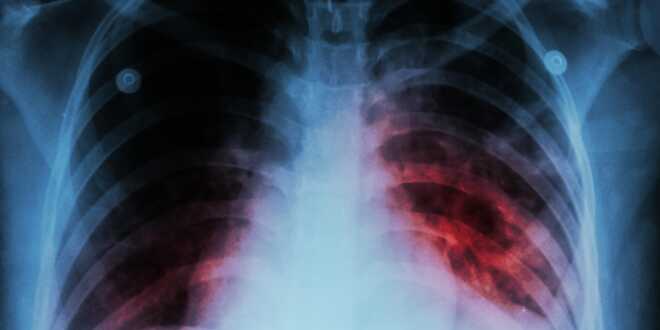

La tuberculosis es una enfermedad contagiosa, que es producida por un bacilo llamado mycobacterium, el cual es transmitido a través del aire y que su principal característica es la aparición de una especie de nódulos en los tejidos que son atacados por el microorganismo.

Es una patología muy grave, que daña rápidamente cualquier órgano del cuerpo, principalmente los pulmones, provocando síntomas como tos, que puede tener presencia de sangre y una notable disminución de peso.